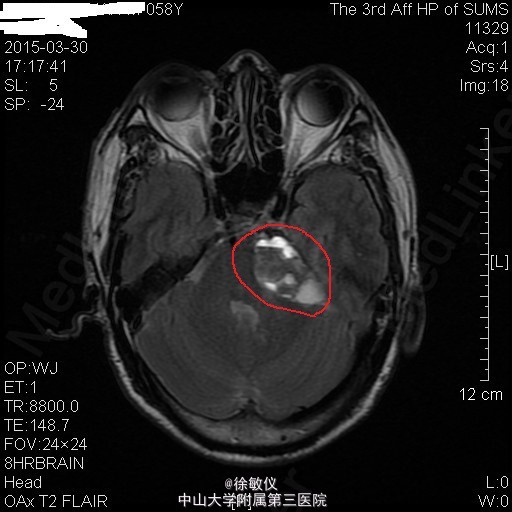

老年患者,主诉:左耳耳鸣、听力下降8年,伴头痛2个月。 现病史:患者8年前始无明显诱因反复出现左耳耳鸣,自诉如鞭炮样鸣响,伴听力进行性下降,无耳道流血流液,可自行缓解。患者曾至当地医院就诊,保守治疗后改善不明显。2个月前始患者出现阵发性全头痛,偶伴头晕、恶心,近2周呕吐胃内容物2次,无发热,无肢体活动异常等不适。于当地医院行头部CT,结果提示:左侧桥小脑角区占位性病变伴出血,听神经瘤(神经鞘瘤)可能性大。患者为进一步治疗来我院。

查体:左耳听力缺失,右耳听力正常。余查体无特殊。 辅查:头部MR:1、左侧桥小脑角区占位病变,考虑为听神经瘤并出血、囊变,病变与左侧听神经、椎动脉关系密切;2、颅脑MRA示脑动脉未见异常。 头部CT:双侧额顶枕叶、半卵圆中心、侧脑室周围、放射冠、基底节区及右侧岛叶多发密度灶,考虑缺血变性灶;颅脑CTA示肿瘤与左侧椎动脉关系密切。